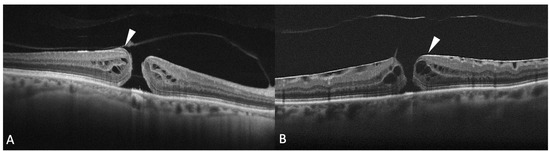

It has been reported that FTHM can be associated with the presence of epiretinal proliferation, also known as atypical epiretinal tissue, identified in structural OCT. Epiretinal proliferation presents as a premacular tissue with homogenous medium reflectivity over the internal limiting membrane on OCT and it is distinct from a hyperreflective tractional epiretinal membrane (Figure 5). Although it is most frequently associated with a lamellar hole, some cases of FTMH also show atypical epiretinal tissue at the edge of the hole. FTMHs with epiretinal proliferation have been reported to have worse clinical and surgical outcomes than FTMH without it [43]. The imaging and histopathological findings imply that the development of FTMH with epiretinal proliferation may not be reconducted to vitreomacular traction. Instead, FTMH with atypical epiretinal tissue might have evolved from lamellar holes with atypical epiretinal tissue. Bae et al. also explored the presence of atypical epiretinal tissue in FTMHs and its pathogenic and prognostic significance [44]. The authors studied 225 consecutive eyes of 211 patients who underwent surgery for an idiopathic FTMH. Eyes were divided into two groups according to the presence of epiretinal proliferation. It was found in 11.6% of the eyes. At baseline, eyes with atypical epiretinal tissue more frequently had a splitting of the inner retina but fewer intact photoreceptors compared with eyes without it. The presence of atypical epiretinal tissue was associated with moderately poorer outcomes at 12 months after surgical treatment, probably due to a large number of defects in the ELM, EZ, and IZ observed postoperatively. So, the authors hypothesized that the presence of epiretinal proliferation in an FTMH was related to poorer anatomical success and less visual recovery after surgery, suggesting that it reflects a chronic pathogenic process involving more severe damage to the foveal tissue. Ishida et al. evaluated the presence of preretinal abnormal tissue (atypical epiretinal tissue, perivascular glia, and a preretinal hyperreflective band) in a study on 60 eyes with FTMH, finding it in most eyes (94%) [45]. In 24%, the abnormal tissue was contiguous to the hole. In the others, it was extrafoveal. Eyes with preretinal tissue contiguous to the FTMH had worse baseline VA.

Figure 5.

(A) Optical coherence tomography (OCT) scan showing a full-thickness macular hole (FTMH) accompanied by atypical epiretinal tissue (arrowhead); (B) OCT scans showing a hyperreflective epiretinal membrane associated with FTMH (arrowhead).